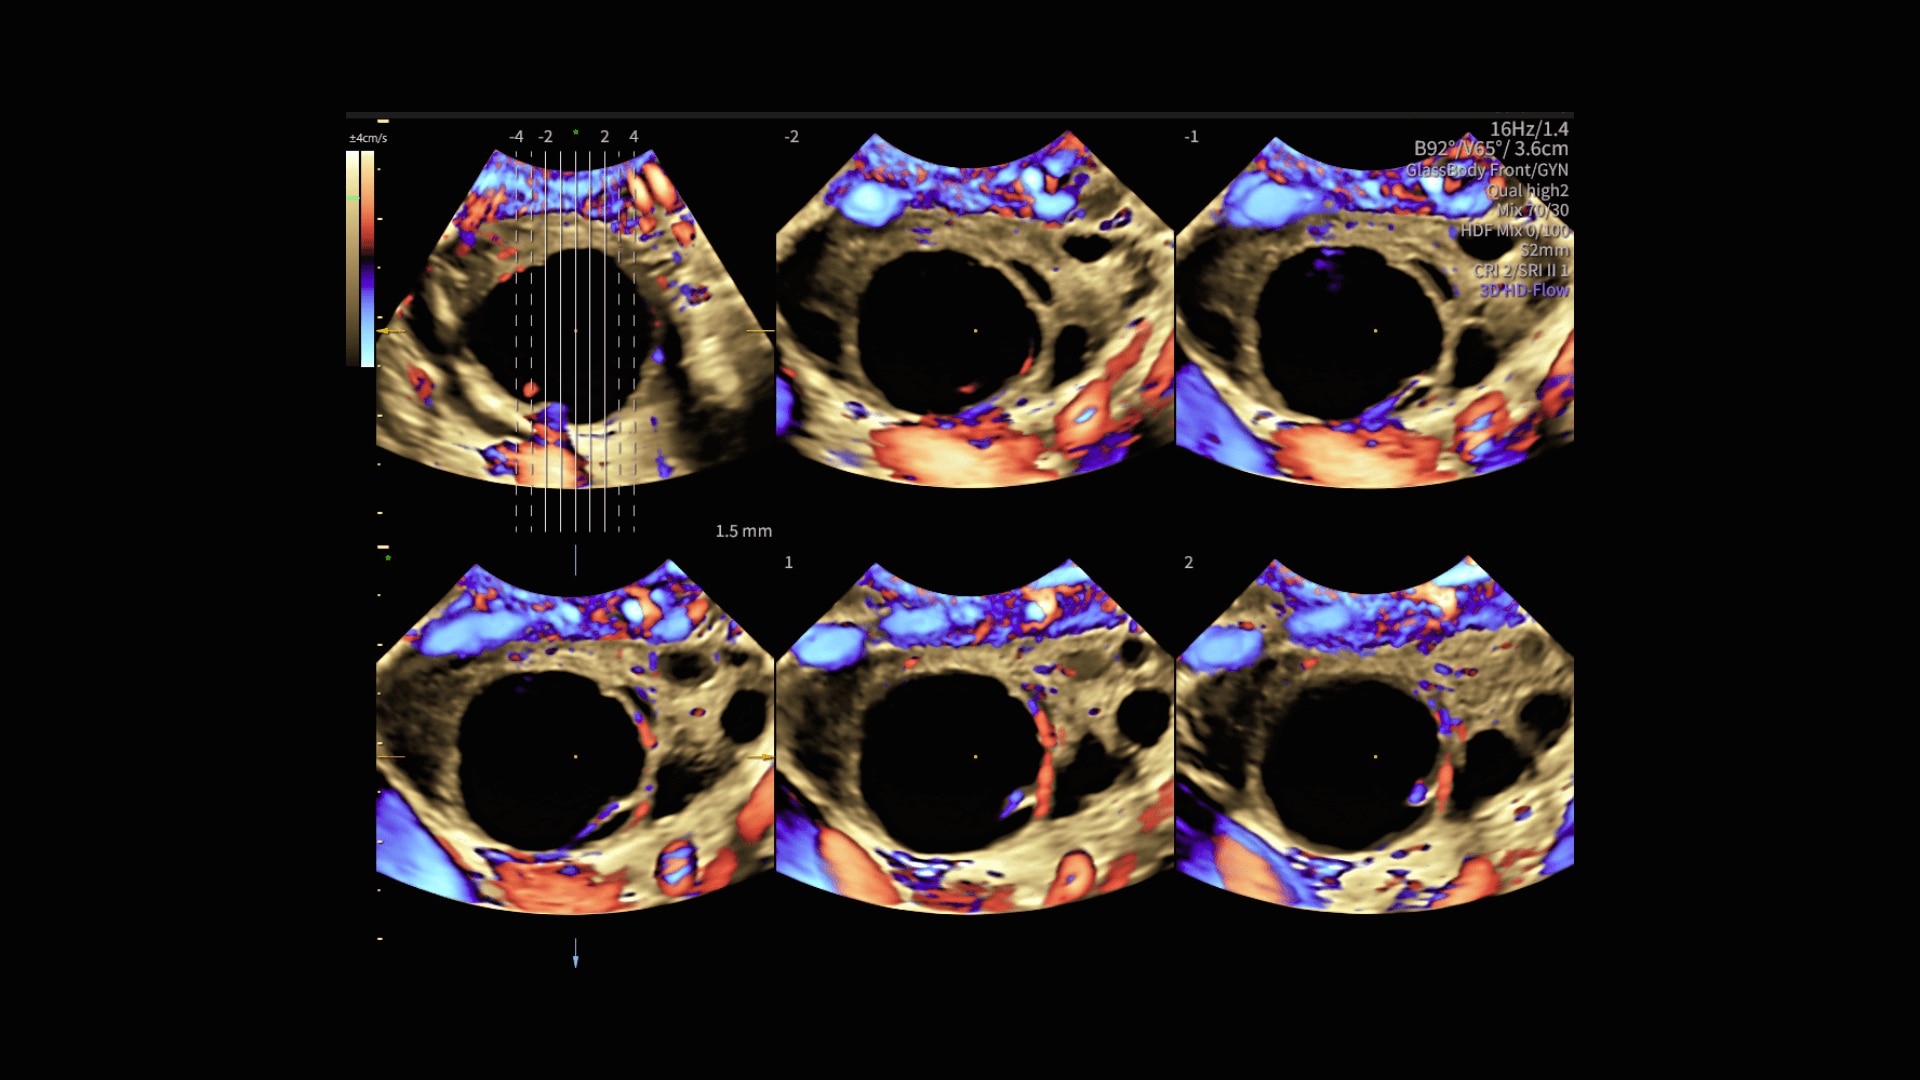

Radiantflow™

Fast, easy 3D-like blood flow visualization

Radiantflow delivers exceptionally sensitive, next level color Doppler for easy fast visualization of blood flow revealing even the tiniest vessels.